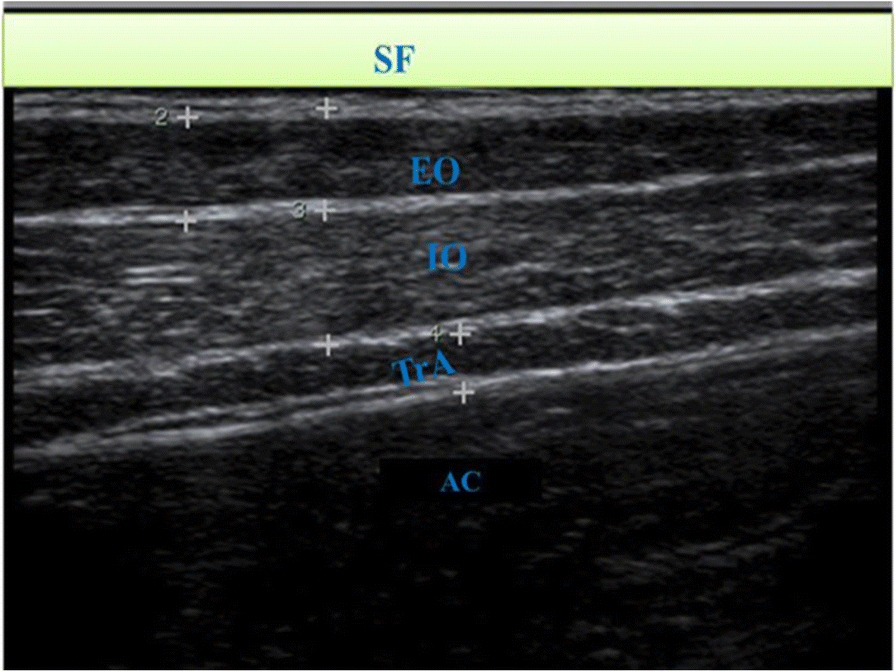

Fig. 1From: An ultrasonographic analysis of the activation patterns of abdominal muscles in children with spastic type cerebral palsy and in typically developing individuals: a comparative studySonogram showing the three anterolateral muscles. SF = skin and superficial fascia, AC = abdominal cavity. The RA is out of viewBack to article page